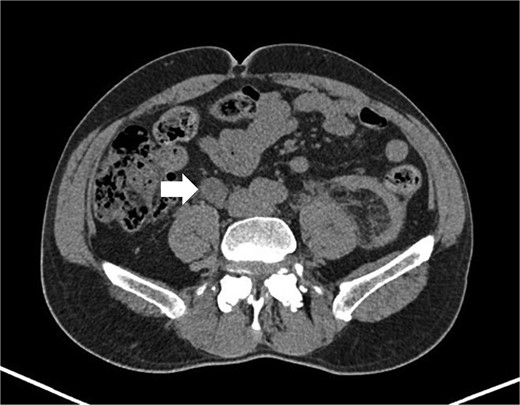

A 64-year-old man with a history of type 2 diabetes, dyslipidemia, and benign prostatic hyperplasia presented to the emergency department following a bicycle accident, resulting in left lumbar trauma. During the patient’s evaluation, an abdominal-perineal computed tomography (CT AP) was requested, which revealed: “Left perirenal hematoma without evidence of active extravasation. A 20x27x24mm nodule (T X AP X CC) in the right para-caval region, approximately at the level of the convergence of the common iliac veins, with heterogeneous and progressive enhancement, possibly indicating a paraganglioma/Zuckerkandl organ.” (Figs 1 and 2). The patient was admitted to the Urology department for conservative treatment, with good clinical evolution, and discharged after 5 days.